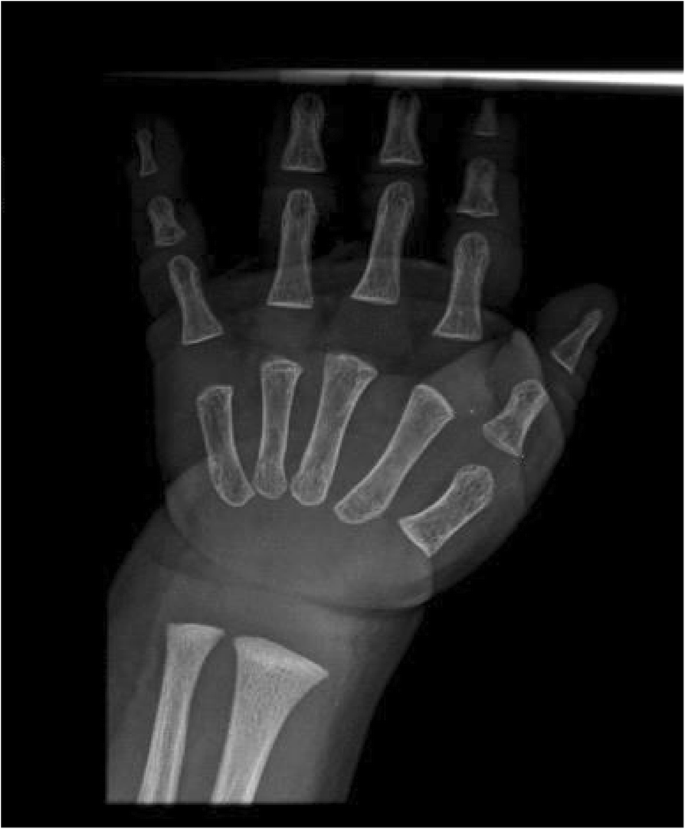

On the occasion of a check-up, at the age of 17 months, we noticed that patient’s mother shared the same facial features of the baby, and presented sparse hair and small hands. She was 158 cm tall. Extending the family history, we found out that the maternal grandfather and the two uncles presented short stature, had the same bulbous nasal tip and thin hair, furthermore they developed alopecia before the age of 20. This information led us to suspect trichorhinophalangeal syndrome, inherited from the maternal lineage, hence we decided to reevaluate the radiograph of the left hand previously made, which revealed a cone-shape appearance of the last phalanges (Fig. 3). Furthermore, we perform a radiograph of the hands of patient’s mother, which showed cone-shaped epiphyses of middle phalanges of 2nd, 3rd and 4th fingers bilaterally, clinodactyly of the 2nd finger bilaterally, brachymetacarpalia of 5th metacarpal bilaterally, with dysmorphic aspect of distal epiphyses (Fig. 4 a, b). All of these radiographic features were consistent with the hypothesis of trichorhinophalangeal syndrome.

Radiograph of the mother’s left hand with morphologic study. a Cone-shaped epiphyses of middle phalanges, clinodactyly of 2nd finger, and brachymetacarpalia of 5th metacarpal. b Morphologic radiographic study: several bone segments are below − 2. Standard Deviation (SD): particularly, the fifth metacarpal bone is below − 5 SD

Imaging studies, especially of the hands, could be useful. Radiographic features include: cone-shaped epiphyses of the middle phalanges of the hands and feet, present in almost all individuals with TRPS and detectable typically after 2 years of age, when epiphyses are just forming; short metacarpals and short phalanges; clinodactyly. Radiographic studies of pelvis and hip resulted often unspecific, showing hip anomalies such as coxa vara, coxa plana, and coxa magna, Perthes disease-like femoral head changes. Multiple exostoses of long tubular bones are typical of TRPS II [13, 14].